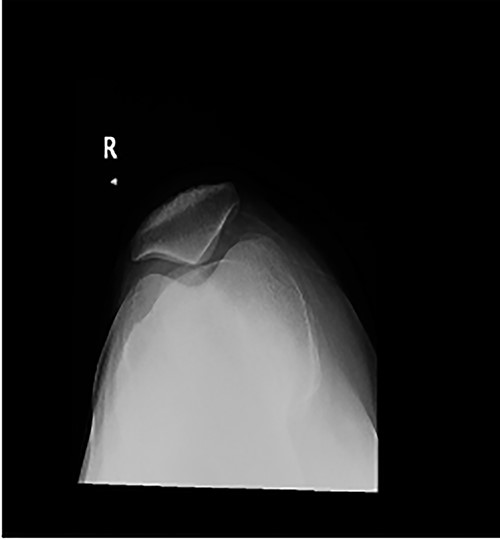

A 48-year-old male was suffering from left knee pain disabling him from doing his daily activities. Twenty-five years prior to presentation, the patient had undergone distal femoral extension osteotomy and tendon transfer as treatment of poliomyelitis orthopedic sequalae. Physical examination revealed left knee genuvarum, medial joint line tenderness and 20–100° for active flexion and 0–110 for passive flexion. Active range of motion (ROM) was only achievable with gravity elimination (Fig. 1). The patient adapted to weakness of his extensors (two-fifths musle powering system of the normal extensor strength) and hip flexors by adopting a gait pattern that involved circumduction of the whole left lower extremity.

Long weight-bearing knee radiographs showed severe osteoarthritic changes, 18° knee genuvarum and extension deformity of the left distal femur (Fig. 2). Skyline view showed severe arthritic changes (Fig. 3).